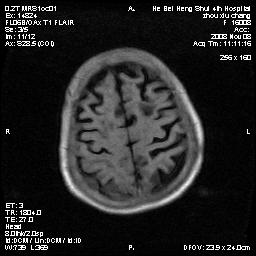

标题: MRI1883:女67岁,半年前曾患脑梗塞,治疗后好转,近3各月精 [打印本页]

女67岁,半年前曾患脑梗塞,治疗后好转,近3各月精神恍惚。

多发硬化(年龄不太支持)待排转移瘤

形态及整体病灶看起来首先考虑转移瘤或淋巴瘤,但奇怪的是多个病灶周围均未见显著的水肿区,这不符合这两个肿瘤的特点,结合ct表现及患者病史有个人考虑是否有皮层下动脉硬化性脑病伴多发胶质增生可能.

支持:皮层下动脉硬化性脑病伴脱髓鞘改变。